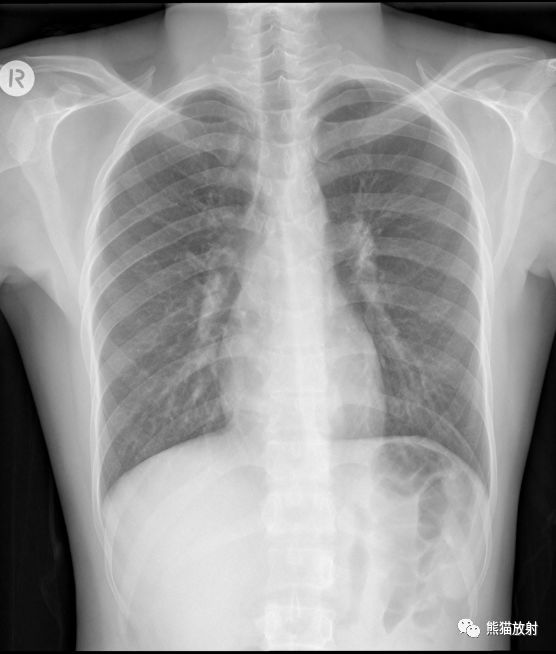

(1)T11椎体转移瘤(胸椎正位片可见T11左侧椎弓根缺如)。